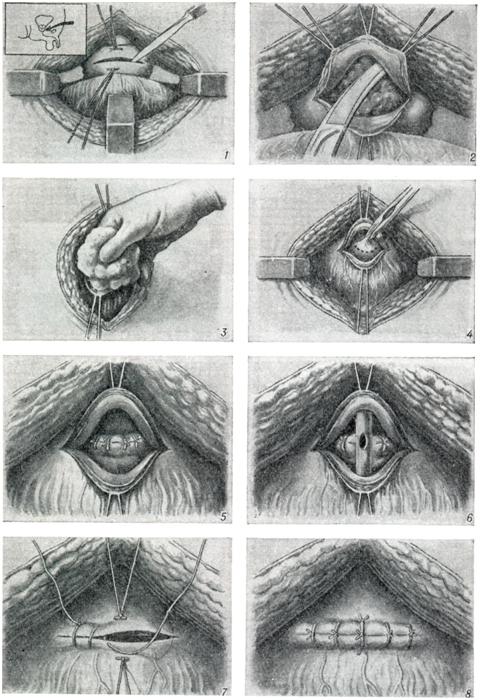

Двухмоментная чреспузырная операция по Хольцову. Эта операция показана ослабленным больным с плохой почечной функцией, когда требуется длительное дренирование мочевых путей. Первый этап — наложение надлобкового свища на срок, необходимый для улучшения функции почек (от 3 недель до 6 месяцев). Второй этап — чреспузырная энуклеация аденомы. Недостаток этого типа операции — необходимость оставления дренажа на длительный срок.

Одномоментная чреспузырная аденомэктомии по Федорову — Фрейеру (рис. 10). Эта операция отличается простотой подхода; летальность при ней около 2,0% . Она дополнена рядом приемов, направленных на обеспечение гемостаза путем наложения швов на края простатического ложа или ушивания его. Гемостаз при этой операции обеспечивается также применением катетера с баллоном типа Померанцева — Фолея (рис. 11). Уменьшение крово-потери ведет к уменьшению таких послеоперационных осложнений, как сепсис или почечная недостаточность.

3. Операция по методу Харриса — Гринчака (рис. 12) заключается вушивании простатического ложа после аденомэктомии под контролем глаза вокруг предварительно введенного катетера: удалив ткани, оставшиеся после энуклеации, на края простатического ложа накладывают швы бумеранговой иглой или обычной значительно изогнутой иглой на длинном иглодержателе. Если кровотечение полностью остановлено, пузырь может быть ушит наглухо; внижний угол раны на 2 суток вводят небольшой резиновый или марлевый выпускник. Постоянный катетер обеспечивает эвакуацию мочи в течение 10 дней. Этот метод дает хорошие результаты при тщательном послеоперационном уходе, особенно впервые 2 суток после операции:каждые 2 часа пузырь промывают теплым изотоническим раствором хлорида натрия или 3,8% раствором лимоннокислого натрия для предотвращения образования кровяныхсгустков.

4. Позадилобковая аденомэктомия(рис. 13) впервые предложена А. Т.Лидским и разработана Миллином(Т. Millin). Операция эта длительноевремя конкурировала с операциейХарриса.

В настоящее, время ее применяют реже из-за наблюдавшихся осложнений — до 15% . Больного укладывают в положение Тренделенбурга с разведенными ногами; подход к предстательной железе осуществляется через вертикальный или поперечный надлобковый разрез. Брюшинную переходную складку отводят вверх; позадилобковую клетчатку осторожно отводят вниз и латерально, избегая обнажения задней поверхности лобкового сочленения. Большие вены, лежащие в фасции на передней стороне предстательной железы, рассекаются между лигатурами. Собственную капсулу предстательной железы вскрывают поперечным разрезом на 1 см ниже шейки мочевого пузыря.

Аденому предстательной железы удаляют из капсулы частично длинными кривыми ножницами, частично пальцем, выделяя ее вплоть до стенки мочевого пузыря; пересечением центральной части мочеиспускательного канала у самой шейки мочевого пузыря удаляют опухоль.

Для предупреждения обструкции после аденомэктомии иссекают манжетку слизистой оболочки из задней дуги шейки мочевого пузыря. Гемостаз обеспечивают диатермией, а также наложением постоянного шва на рану в простатической капсуле; последнее очень важно. После тщательного гемостаза через мочеиспускательный канал в мочевой пузырь вводят катетер № 18—22 (по Шаррьеру) с большими отверстиями на конце. Над катетером послойно ушивают рану, в нижний ее угол на 48 часов вводят резиновый выпускник.

5. Промежностную аденомэктомию по Янгу (рис. 14) в наст, время почти не применяют из-за опасности возникновения осложнений: недержания мочи, промежностных свищей, импотенции. Возникновение этих осложнений при промежностном подходе вполне объяснимо, так как аденому удаляют через каудальную зону простаты, тесно связанную с тканями наружного сфинктера.